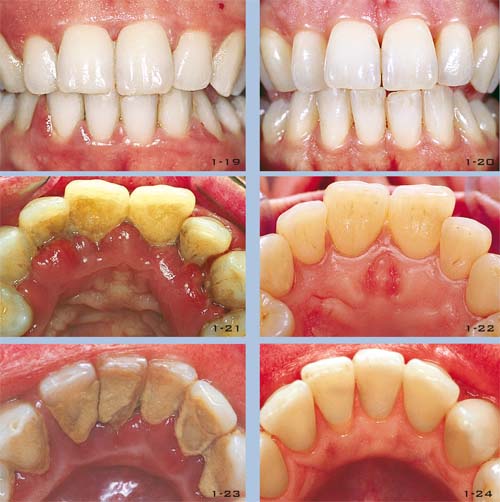

Nun liegen wichtige klinische Befunde vor: Röntgenstatus (mindestens 16 Bilder) (Abb. 1-10 bis 1-14 und 1-18), Panoramaaufnahmen (Abb. 1-15 bis 1-17), Parodontalstatus (Abb. 1-9) und vor allem Information über die Fähigkeiten und den Willen des Patienten zu einer effektiven Plaquekontrolle (Abb. 1-19 bis 1-24).

Entsprechend den klinischen Notwendigkeiten und der Disposition für orale Erkrankungen (Karies, Parodontitis) des jeweiligen Patienten kann ein individuelles Hygieneprogramm entwickelt werden (Abb. 1-25 bis 1-29).

Abb. 1-19 bis 1-24 Die Motivation des Patienten ist die Basis jeder Behandlung, sei sie einfach oder komplex. Regelmäßige professionelle Reinigung, angepasst an die Bedürfnisse des Patienten und ein Leben lang, muss sich an jede Behandlung anschließen. Diese Bilder zeigen einen klinischen Fall: eine 30-jährige Frau, bei der eine Vorbehandlung und eine resektive Parodontalbehandlung durchgeführt wurden. Die Bilder zeigen den klinischen Zustand vor (Abb. 1-19, 1-21 und 1-23) und nach (1-20, 1-22 und 1-24) der Behandlung. Parodontal gesunde Verhältnisse sieben Jahre nach Abschluss der Behandlung, festgestellt in einer Recall-Sitzung. Abb. 1-25 und 1-26 Nicht chirurgische Behandlung einer Gingivarezession vor und ein Jahr nach der Behandlung. Das creeping attachment wurde nicht chirurgisch in verschiedenen Sitzungen erreicht. Abb. 1-27 ähnlicher klinischer Fall, der auch nicht chirurgisch gelöst wurde. Abb. 1-28 Abheilung nach sechs Monaten. Abb. 1-29 Stabiler parodontaler Zustand nach acht Jahren: entzündungsfrei und ohne Rezidiv.